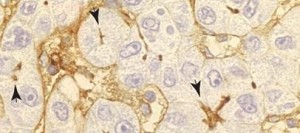

y funcionales. Inmunohistoquímica de un hígado infectado con el virus de la hepatitis C

Según Jaime Millán, científico del CSIC y director el estudio, y Natalia Reglero-Real, primera firmante del artículo, cuando las células epiteliales hepáticas pierden su forma, ICAM-1 se dispersa del dominio apical y se expone a otras células, favoreciendo la adhesión de los linfocitos. Al contrario, cuando se incrementa farmacológicamente la polarización de estas células, ICAM-1 se confina en el dominio, y la adhesión de los linfocitos T disminuye. Este fenómeno de polarización y despolarización de ICAM-1 se ha observado en muestras de hígado de pacientes con infecciones de hepatitis B y C y en hígados trasplantados que han sufrido un rechazo inmunitario.